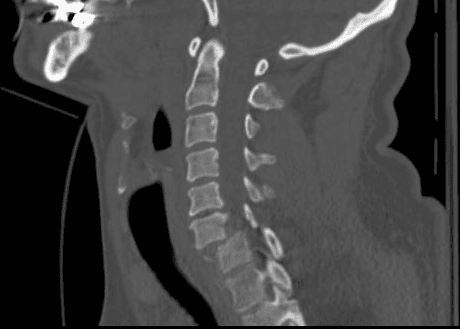

Tραυματικό εξάρθρημα Α6-7 με συνοδό τετραπληγία.

Ο ασθενής προσήλθε μετά από πτώση από ύψος με αδυναμία στα άνω άκρα και πλήρη ακινησία στα κάτω άκρα. Η πρόγνωση βάση της αρχικής νευρολογικής εικόνας θεωρήθηκε πτωχή.

Μετεγχειρητική μαγνητική τομογραφία με τον ασθενή σε σταδιακή βελτίωση και ίαση.

Η βελτίωση του ασθενούς μετεγχειρητικά ήταν σταδιακή και εντυπωσιακή. Ακολούθησε ειδικό πρόγραμμα μηνών σε κέντρο αποκατάστασης και αναμένεται πλήρης λειτουργικότητα.